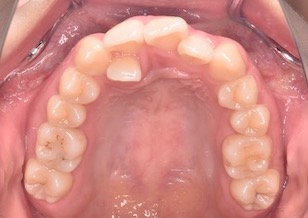

矯正前

Before Ⅰ

上下顎歯列に重度の叢生(ガタガの歯並び)を認めます。下顎の右側側切歯は先天欠如を認めました。上顎右側側切歯は舌側に転位し反対咬合になっています。

また左側の上下顎第1大臼歯がすれ違い(交叉咬合)となっています。~すれ違い咬合の改善は難易度が高い治療となります。~